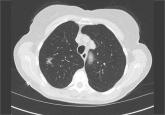

Pulmonary nodule on x-ray: An algorithmic approach

The best way to manage a pulmonary nodule depends on the patient's history, risk factors for cancer, and nodule characteristics. This review can...

For years, I was taught there was no effective way to detect early-stage lung cancer. However, the National Lung Screening Trial provides evidence that routine low-dose computed tomography (CT) screening can be effective, provided the guidelines are followed strictly and the operative morbidity and mortality is sufficiently low.1 This is certainly a practice-changer, but balancing risks and benefits of CT screening also depends on judicious management of the “incidentalomas” that are discovered, as described in the article by Yunus and Mazzone. (See “Pulmonary nodule on x-ray: An alogrithmic approach”.)